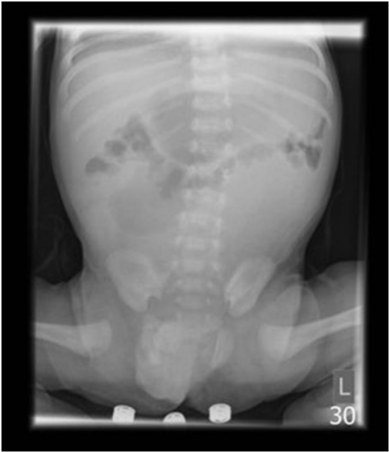

A term male infant conceived via In vitro fertilisation, presented with bile-stained vomiting 2 days after discharge from the maternity unit. Observations on admission were within normal parameters, and the abdomen was non-distended. An abdominal film revealed duodenal and proximal jejunal distension, with paucity of small bowel gas distally (Figure 1). The patient was taken to theatre with a tentative diagnosis of jejunal stenosis.

Figure 1 Abdominal radiograph demonstrating distended stomach and proximal small bowel with paucity of distal gas, suggestive of jejunal stenosis.